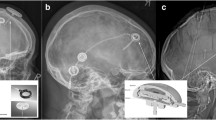

In patients who developed a secondary hydrocephalus (sNPH) a VP shunt (VPS) with sensor reservoir® was implanted (Fig. 1). All patients with apparent potential for rehabilitation received adjustable pressure valves (proGAV, Aesculap-Miethke, Potsdam, Germany) with fixed gravitational valves (between 200 and 300 mm H2O according to body size).

Coronar reformation of a cerebral CT after implantation of a NEUROVENT®-P-tel probe through a right frontal burr-hole and a sensor reservoir® connected to a ventricular catheter through a left frontal burr-hole. (Institute for Radiology and Neuroradiology at the Unfallkrankenhaus Berlin, Director Prof. Dr. med. S. Mutze)

In all patients an EVD was placed. In eight patients a NEUROVENT®-P-tel probe was implanted within the same session. Eleven of the 16 patients developed a secondary hydrocephalus and required VPS implantation: all patients of “P-tel + EVD group” (n = 8) and three of “EVD group” (Fig. 2). In these patients a VPS with sensor reservoir® was implanted through a left frontal burr-hole while the NEUROVENT®-P-tel probe was implanted contralaterally in those that did not already have one (Fig. 2).